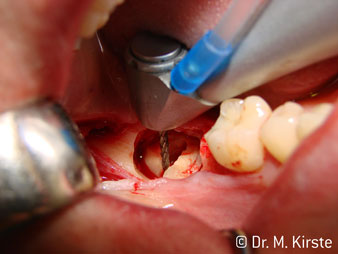

45° ъгъл на наконечника е специално избран поради неговата широка гама от предимства. Колеги, които работят хирургия, и за които този наконечник е главно създаден, скоро ще оценят възможността за ефективна работа в силно ограничени пространства. При екстрахиране на мъдреци, в частност (фиг. 2), няма нужда от голямо разширяване на меката тъкан в областта на бузата (фиг. 3). Дизайнът на главата на наконечника, в съчетание с лекото завъртане на главата по време на препарация, позволява бърза и безопасна работа в ретромоларната област.

Специалният дизайн на лагерите в главата на наконечника гарантира безшумен ход на борера; това прави впечатляващо атравматичен разрез при отделянето на зъба и корена (фиг. 4-9).

45° обратен наконечник е много удобен в ръка. Забелязвате почти веднага, че работната глава имитира ъгъла на вашия показалец и желаното движение просто се прехвърля няколко въображаеми сантиметра паралелно на върха. (Фиг. 1)”